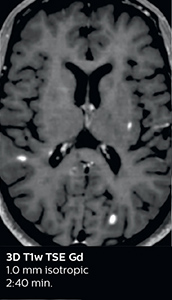

The abbreviated MS protocol for brain is only around 9 minutes, so in case of suspected multiple sclerosis, one or two more advanced sequences may be added, such as PSIR (phase sensitive inversion recovery) or susceptibility-weighted sequences to help us make more confident diagnoses in these inflammatory cases.

In this example, the optional 3D multishot susceptibility weighted sequence with 0.6 mm isotropic voxels is 2 lesions with a central vein sign (arrows) and one lesion with a phase-rim sign (arrowhead). The total scan time, including SmartBrain and axial PD/T2 3mm, is 11:10 min. and is 18:30 min. with the optional 3D PSIR and 3D SWI multishot included.

“We used to have long examination times for certain types of patients, a few lasting more than 40 minutes,” says Dr. Savatovsky. “What is remarkable, is that now all these examinations are below 30 minutes, which opens up opportunity to add more sequences when needed. It’s really hard to keep a patient for more than 40 minutes in the scanner, but because we have now cut scan times by at least 10 minutes, we can add more sequences without making the exam too long. And this is where the new system helps us make a difference. Examples include our examinations for informing brain tumor classification or giant cell arteritis workup, or for intracranial wall imaging – so in patients where we need several advanced sequences or high resolution sequences.” “We added three additional sequences in our brain neoplasm classification exam: a 3D SWI sequence, APT and ASL on top of 3D morphologic sequences, an isotropic DSC (dynamic susceptibility contrast) and multivoxel spectroscopy. I think that in patients that need a classification for brain mass, for example, we can provide a more detailed and confident diagnosis than before, allowing the clinicians to decide for either a medical workup if no tumor is suspected, or for neurosurgery as soon as possible if a neoplasm is suspected.” “In multiple sclerosis patients, we increasingly include a multishot susceptibility sequence [3] in our routine cases, thanks to the shorter scan times. Our abbreviated MS protocol for brain is around 8 to 9 minutes, so we can ask for one or two additional sequences to visualize the central veins, or to get an additional contrast to better depict posterior fossa lesions. In cases of white matter lesions of unknown significance on FLAIR images, for example when we see high signal hyperintensities in the brain, we can add on more advanced sequences such as PSIR (phase sensitive inversion recovery) or susceptibility-weighted sequences to help us in distinguishing between MS and nonspecific or vascular abnormalities in these inflammatory cases.”